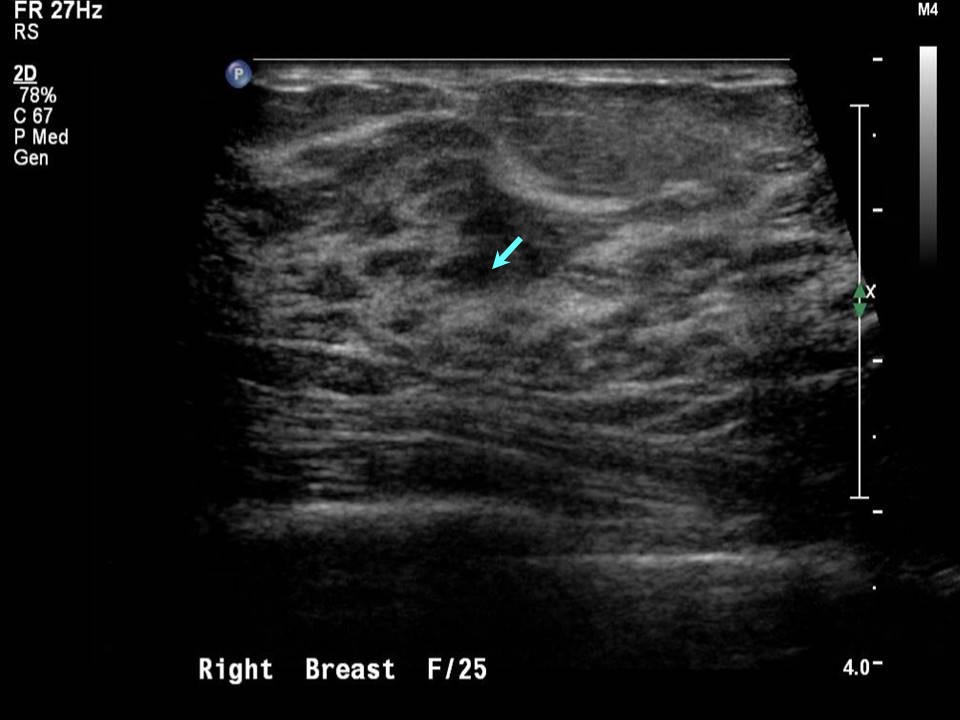

From screening.iarc.fr

Atlas of breast cancer early detection What Does Echotexture Mean What does it mean to have an ‘echogenic liver’? The appearance can be normal or heterogeneous due to some myometrial pathology, for. Morrey's the elbow and its. Echotexture refers to the visual representation of the liver’s ultrasound image. It can be caused by inflammation, fibrosis, cysts, tumors, or scarring, and. This refers to the brightness of the tissue. Various conditions. What Does Echotexture Mean.

Atlas of breast cancer early detection What Does Echotexture Mean Various conditions lead to coarse. The appearance can be normal or heterogeneous due to some myometrial pathology, for. Coarse echotexture, marked by increased sound scattering, indicates underlying liver disease. It can be caused by inflammation, fibrosis, cysts, tumors, or scarring, and. What are the possible causes? This refers to the brightness of the tissue. A fine or homogeneous echotexture indicates. What Does Echotexture Mean.